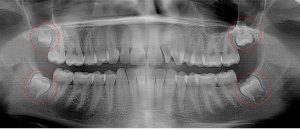

This 21 year old patient has all four 3rd molars present (circled). The roots are approximately 2/3rds formed. The lower right 3rd molar cannot erupt any further; it is distally tipped into the ramus of the mandible. The lower left 3rd molar likely will not erupt any further; it is pushing into the undercut of the distal of the 2nd molar.